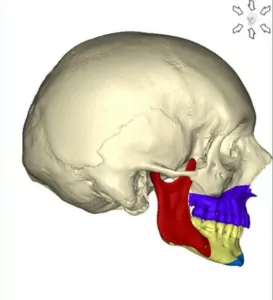

Les ostéotomies totales

Le chirurgien réalise une interruption totale d’une pièce anatomique ; maxillaire, mandibule.

L’ostéotomie de Lefort 1

Le chirurgien réalise une interruption totale entre le maxillaire et le reste du massif cranio-facial.

L’ostéotomie de Lefort 1 permet de déplacer la totalité du maxillaire supérieur c’est à dire l’ensemble « os basal – os alvéolaire – dents supérieures » dans les 3 dimensions de l’espace.

L’ostéotomie de Lefort 1 peut aussi être réalisée en un, en deux fragments ou en trois fragments pour permettre une mobilisation différente pour chacun des fragments du maxillaire. Il peut s’agir d’une expansion transversale lorsque le maxillaire est trop étroit transversalement. Il peut s’agir de mouvements spécifiques pour chacun des fragments maxillaires comme cela est souvent nécessaire en cas d’asymétrie ou de béance.

L’ostéotomie sagittale des branches montantes

Elle permet de déplacer l’ensemble de l’arc denté mandibulaire c’est à dire ensemble de « os basal – os alvéolaire – dents inférieures » dans les trois dimensions de l’espace.

L’ostéotomie de transposition du menton appelée aussi « Génioplastie »

Elle permet de déplacer le menton dans les trois dimensions de l’espace.

Les ostéotomies combinées

Elles permettent d’agir simultanément sur l’ensemble des éléments anatomiques de la face. En pratique toutes les combinaisons d’ostéotomies sont possibles selon l’anomalie observée. L’ostéotomie Bimaxillaire avec Génioplastie est la plus courante. Elle associe une ostéotomie de Lefort 1 en un ou plusieurs fragments, une ostéotome sagittale bilatérale des branches montantes et une génioplastie.

Les Ostéotomies du tiers moyen de la face : l’ostéotomie de Lefort II et l’ostéotomie Lefort III

Elles permettent d’agir à un niveau plus haut situé de la face. Plus rarement réalisées, elles s’adressent aux malformations plus rares qui s’étendent vers l’orbite. La voie d’abords reste esthétique, mixte : endobuccale, trans-conjonctivale (à travers la conjonctive) et coronale (dans le cuir chevelu).

L’ostéotomie de Lefort II intéresse tout le massif facial depuis les dents jusqu’aux nez sans les plancher des orbites et les pommettes.

L’ostéotomie de Lefort III intéresse tout le massif facial depuis les dents jusqu’aux nez avec les planchers d’orbites et les pommettes.

Les associations Lefort III – Lefort I et Lefort II – Lefort I ; dictées par les besoins de l’occlusion, sont fréquentes.